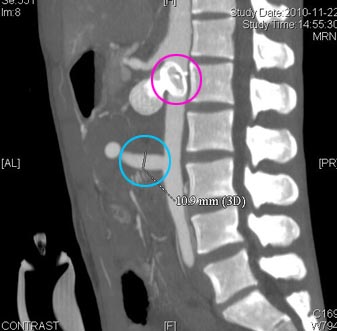

术前(红圈处为“动脉瘤”)

术后(红圈处为“封堵器”,蓝圈处为“人工血管桥”)